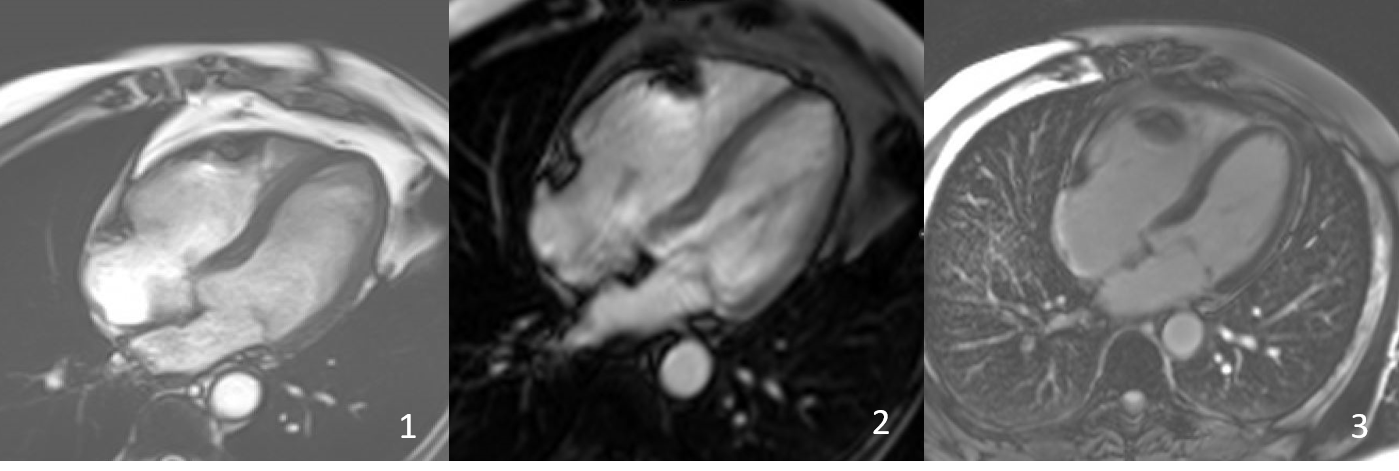

FIG 3- Follow up scan showing 4 Ch cine view in b-SSFP (1)- Early gadolinium enhancement (2) and late gadolinium enhancement (3) demonstrating no mass in the RV.